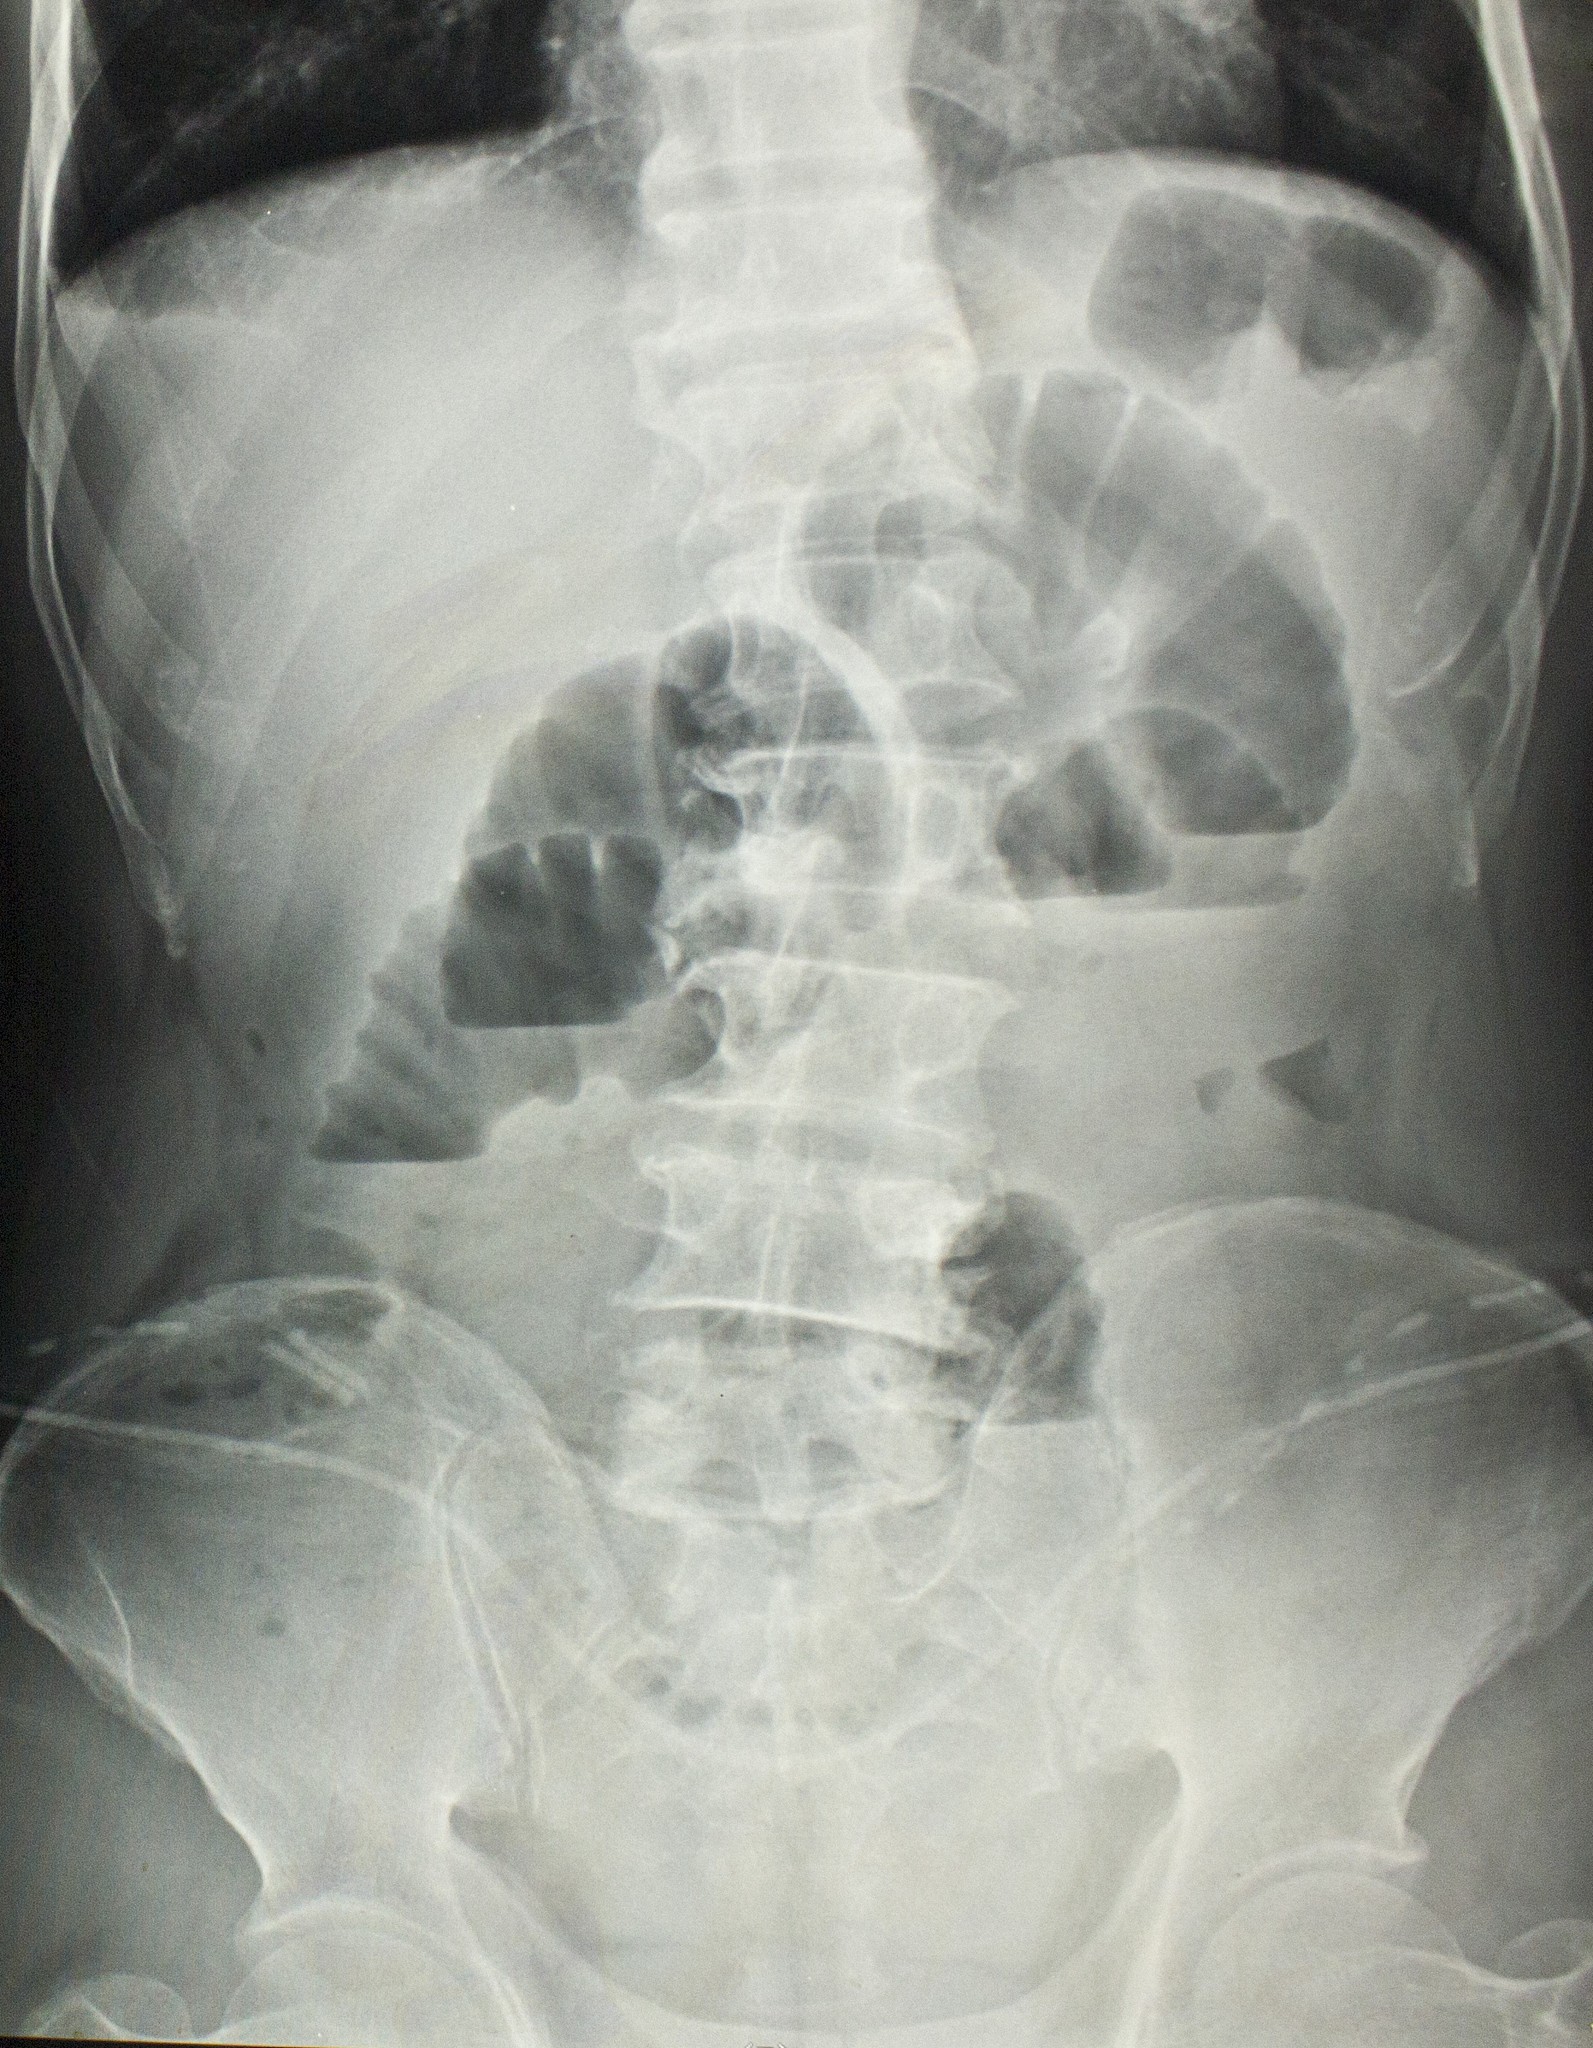

3. 钡堵塞:在胃肠道检查过程中,钡餐可能会堵塞肠道,导致肠梗阻。这种情况较为罕见,但需要密切关注。